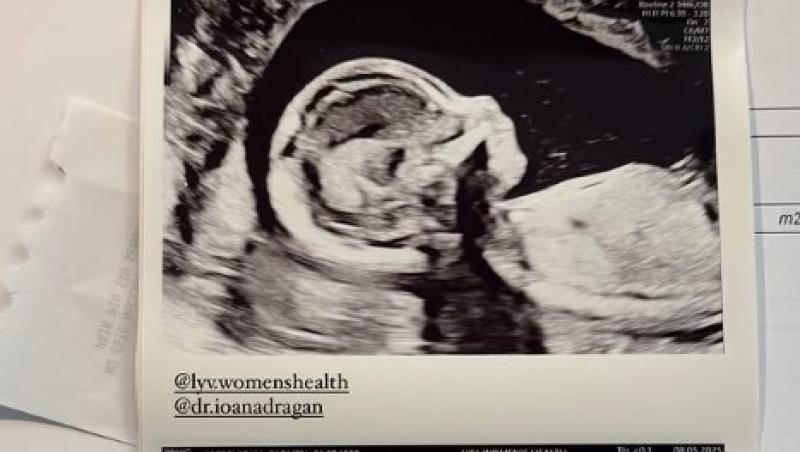

După o perioadă mai dificilă, marcată de un divorț, Carmen Grebenișan a reușit să se vindece și și-a găsit fericirea în brațele noului iubit. În urmă cu puțin timp, ea a postat pe rețelele de socializare primele imagini cu ecografia bebelușului.

Primele imagini cu bebelușul lui Carmen Grebenișan

Nașterea este așteptată în luna septembrie, iar viitorii părinți numără cu nerăbdare lunile rămase până când își vor ține copilul în brațe. Deși nu au dezvăluit încă sexul bebelușului, cei doi urmează să afle în curând și să aleagă și numele potrivit. Până atunci, influencerița le-a arătat urmăritorilor mai multe imagini cu ecografia bebeșului.

„El: Ce suvenir vrem să luăm cu noi, să ne amintească de Miami? Poate un pandantiv, un magnet sau poate o vedere? Ea: Cred că deja am luat cel mai prețios suvenir cu noi”, a mai scris Carmen Grebenișan, înainte de a le arăta internauților ecografia cu bebelușul.